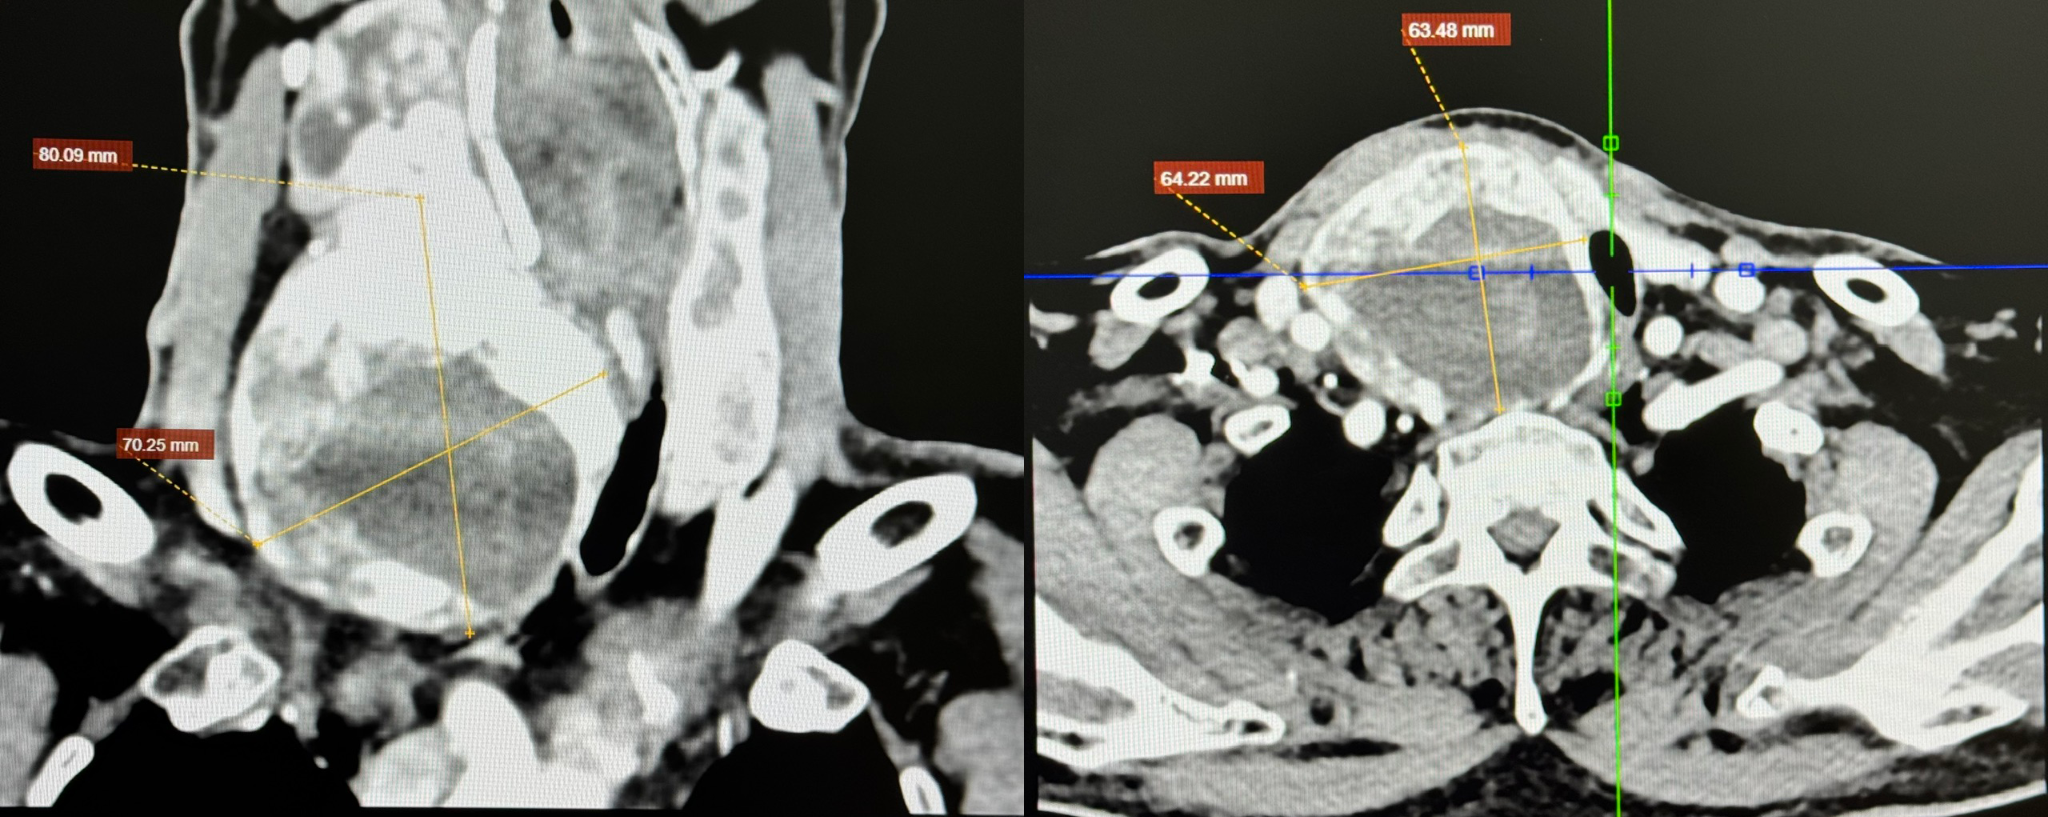

Mr. Ky, 67, presented with hypertension, dyslipidemia, and stage 3 chronic kidney failure. Master of Science, Doctor, Specialist Level I Pham Ngoc Minh Thuy, from the Cardiovascular Surgery Department, Cardiovascular Center, Tam Anh General Hospital TP HCM, reported Mr. Ky's right thyroid lobe measured 68x68x121 mm. This goiter extended into the sternal notch, displacing the trachea and esophagus to the left and narrowing the tracheal lumen to 9 mm, far less than the normal 20 mm diameter.

CT scan shows a large goiter compressing the trachea. *Photo: Tam Anh General Hospital* |

Master of Science, Doctor Tran Thuc Khang, Deputy Head of the Cardiovascular Surgery Department, Cardiovascular Center, explained that an airway narrowed by more than 55% indicates severe compression. The esophagus, located directly behind the trachea, was also displaced, obstructing food passage to the stomach. Patients are at risk of chronic hoarseness, acute dyspnea, tracheomalacia (weakening of the tracheal cartilage rings and loss of elasticity), sleep apnea, and aspiration of food into the airway if not treated promptly.